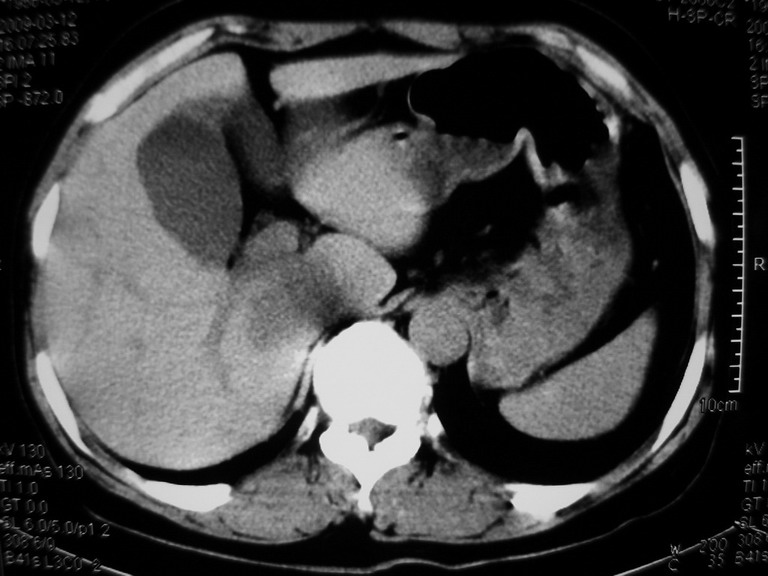

患者,女性50岁,上腹部不适2年余,既往多次腹部彩超未见异常,今日上午在我院查彩超发现肝右叶囊实性病变,外院辅助检查,afp,cea,ca199, 都在正常范围内,无肝炎史否认肿瘤史,生活在牧区

接着往下一贴看,有静脉期和延迟期,在看看和下腔静脉及十二指肠的关系,腔静脉内是不是栓子?

考虑肝右叶与尾叶交界区肝癌(部分外生),侵犯下腔静脉并下腔静脉瘤栓形成。

肝包虫病可能性大